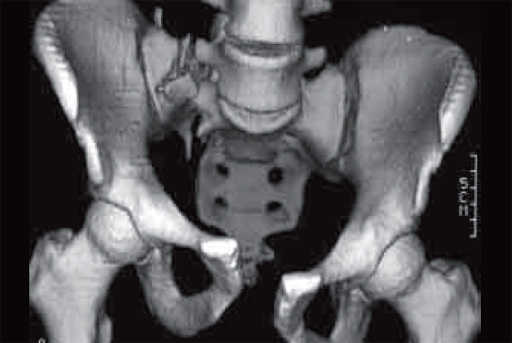

Case new pelvic set

32-year-old man (165 kg), fell 7 meter into stairwell; bilateral open tibial fractures and both column fractures variant.